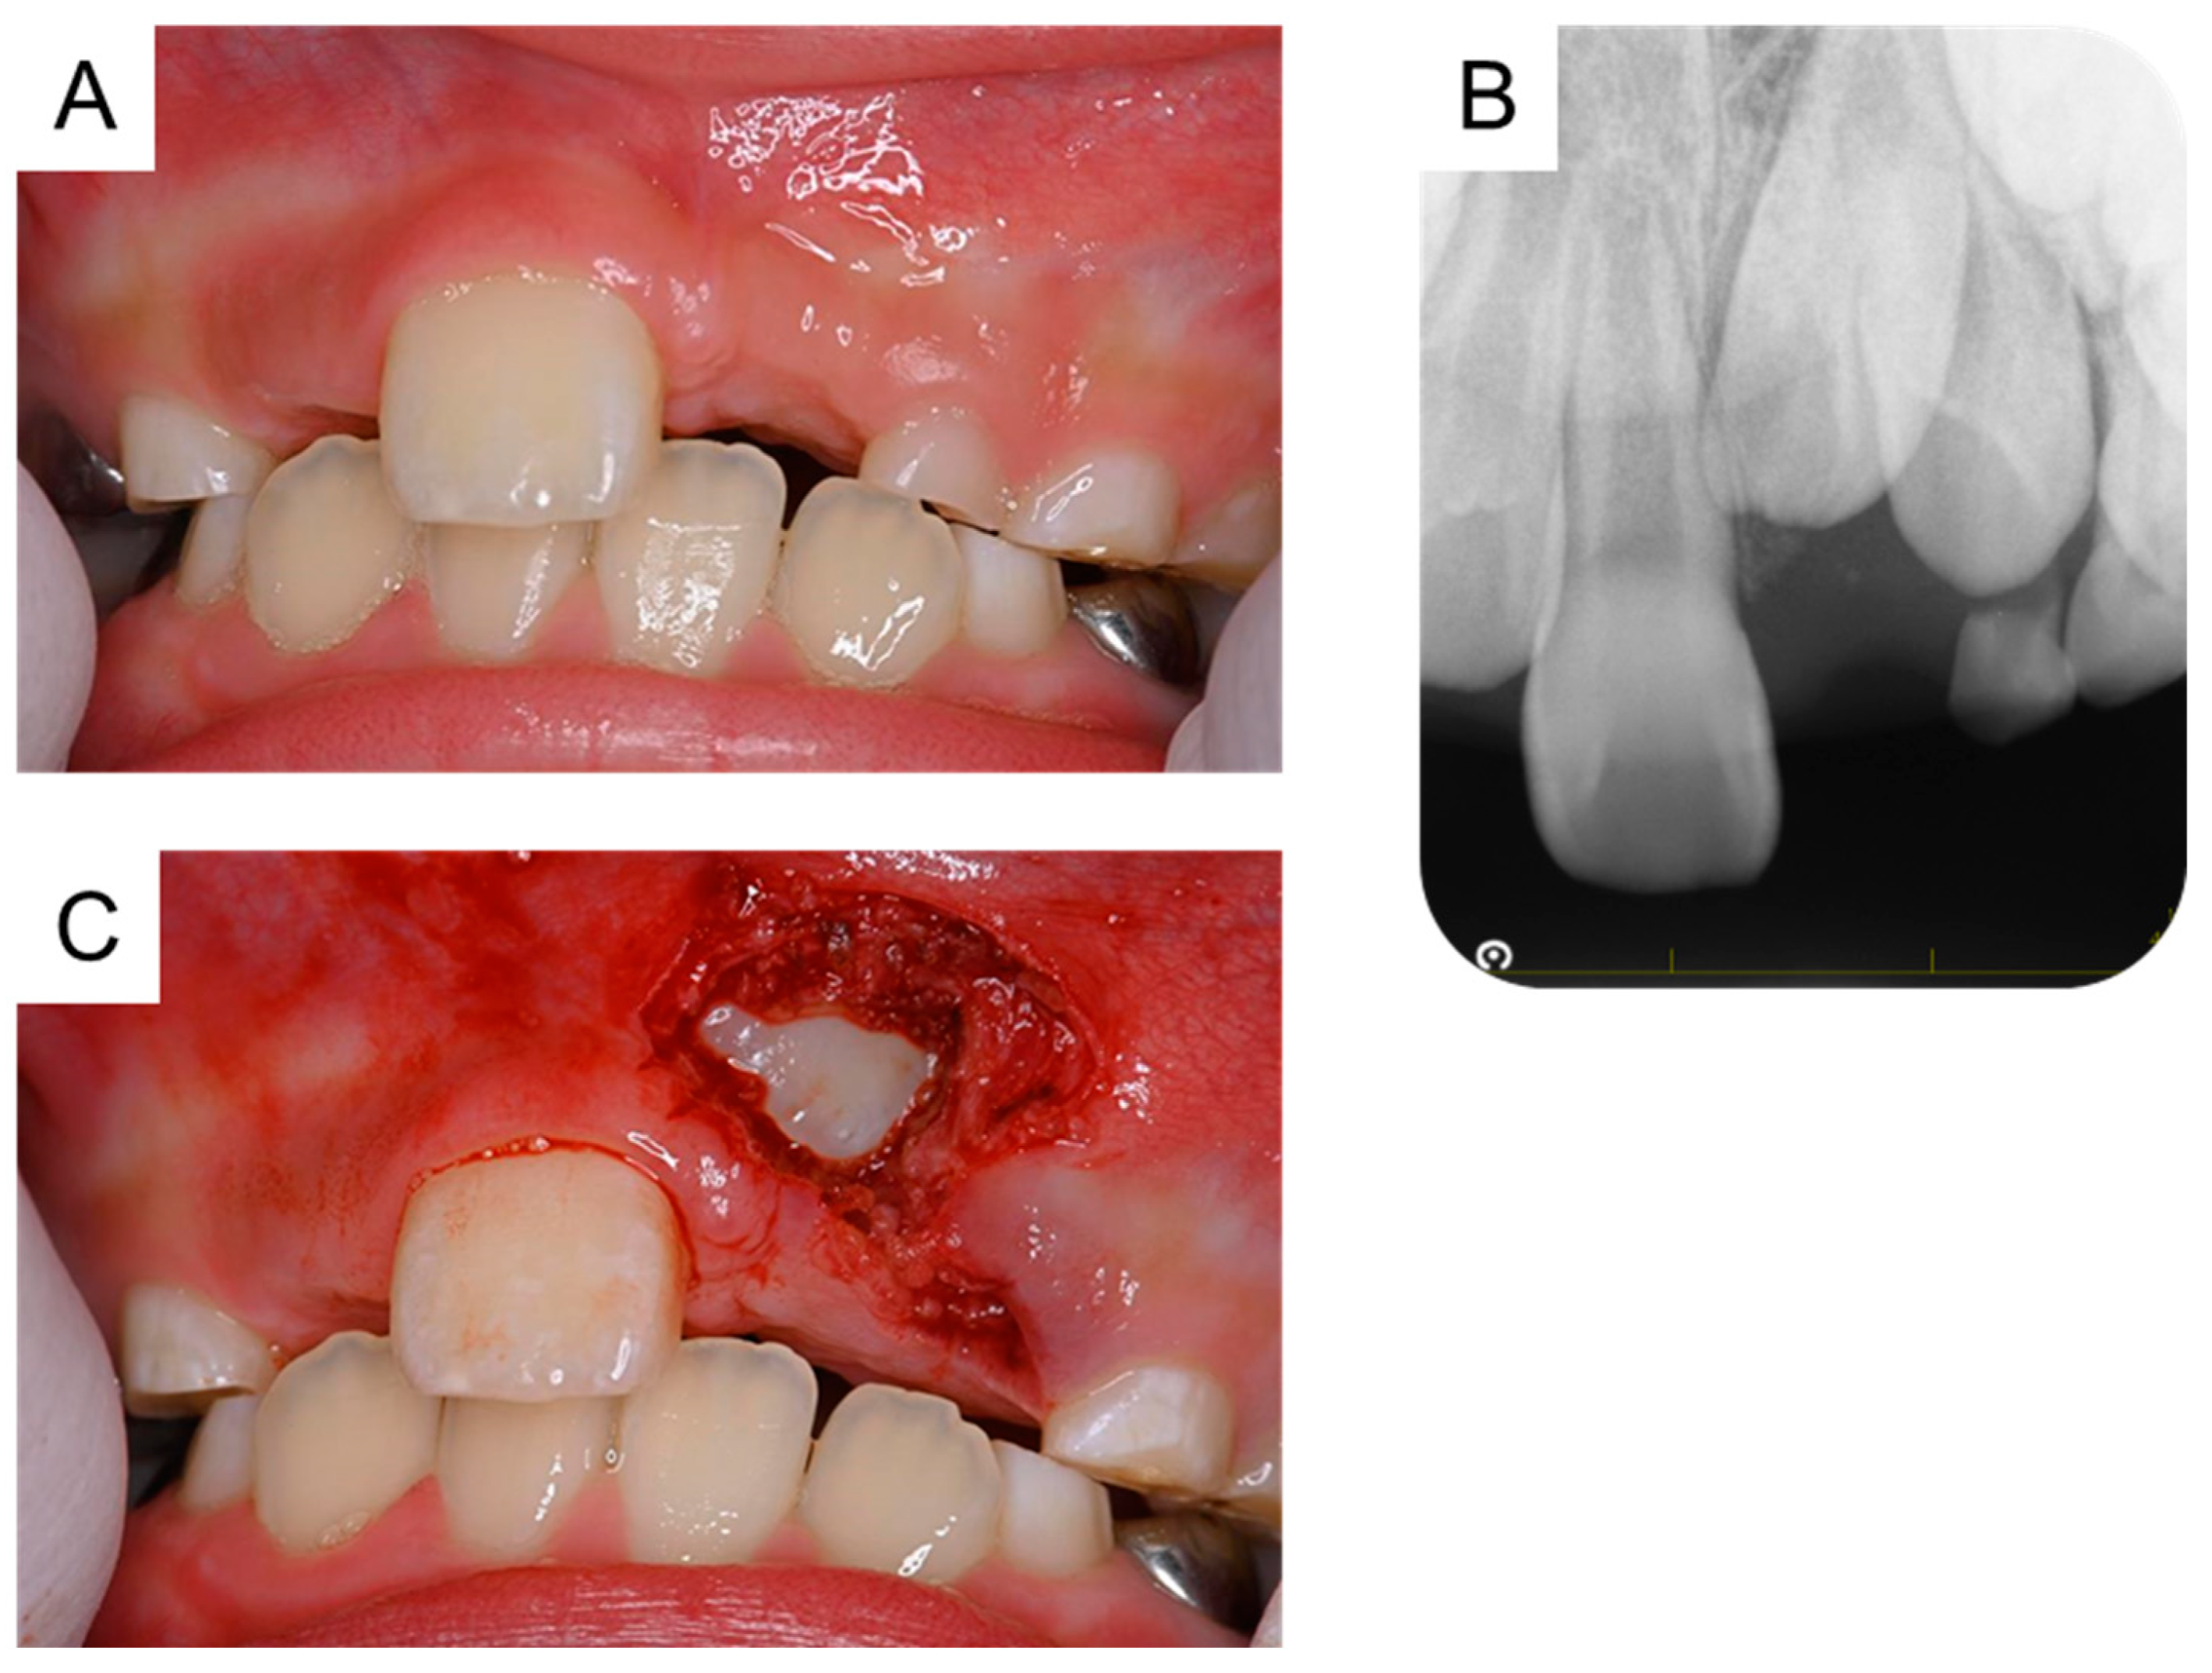

Orthodontic treatment was considered after the extraction of the third supernumerary tooth; however, the patient was uncooperative because of his intellectual disability. At 8 years and 9 months of age, a periapical radiograph revealed no change in the location of the permanent maxillary left central incisor (Figure 5A,B). Thus, under physical restraint and local anesthesia, the gingiva was surgically removed using an electrocautery device to expose the surface of the crown (Figure 5C).

Figure 5. Fenestration of the maxillary left central incisor. (A) Intraoral photograph and (B) periapical radiograph after the extraction of the third supernumerary tooth at the age of 8 years and 9 months. (C) Intraoral image just after fenestration of the maxillary left central incisor at the age of 8 years and 9 months.